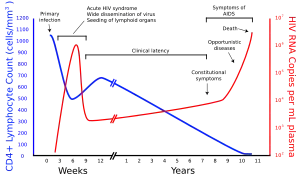

The human immunodeficiency viruses (HIV) are two species of Lentivirus (a subgroup of retrovirus) that infect humans. Over time, they cause acquired immunodeficiency syndrome (AIDS),[1][2] a condition in which progressive failure of the immune system allows life-threatening opportunistic infections and cancers to thrive.[3] Without treatment, average survival time after infection with HIV is estimated to be 9 to 11 years, depending on the HIV subtype.[4] In most cases, HIV is a sexually transmitted infection and occurs by contact with or transfer of blood, pre-ejaculate, semen, and vaginal fluids. Research has shown (for both same-sex and opposite-sex couples) that HIV is untransmittable through condomless sexual intercourse if the HIV-positive partner has a consistently undetectable viral load.[5][6] Non-sexual transmission can occur from an infected mother to her infant during pregnancy, during childbirth by exposure to her blood or vaginal fluid, and through breast milk.[7][8][9][10] Within these bodily fluids, HIV is present as both free virus particles and virus within infected immune cells.

HIV infects vital cells in the human immune system, such as helper T cells (specifically CD4+ T cells), macrophages, and dendritic cells.[11] HIV infection leads to low levels of CD4+ T cells through a number of mechanisms, including pyroptosis of abortively infected T cells,[12] apoptosis of uninfected bystander cells,[13] direct viral killing of infected cells, and killing of infected CD4+ T cells by CD8+ cytotoxic lymphocytes that recognize infected cells.[14] When CD4+ T cell numbers decline below a critical level, cell-mediated immunity is lost, and the body becomes progressively more susceptible to opportunistic infections, leading to the development of AIDS.